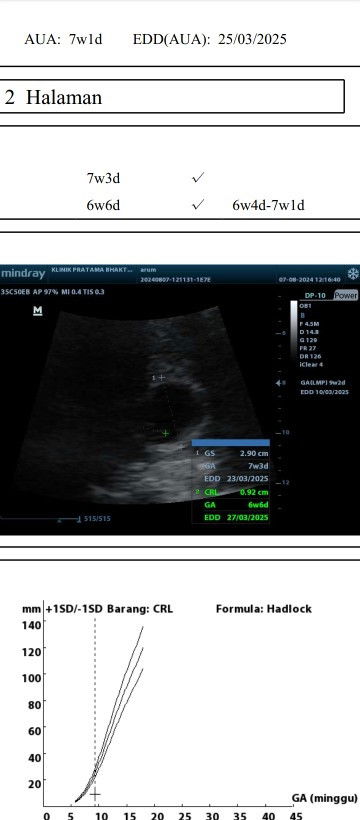

Hamik 7week besok

Bunda bunda sharing dong,aku prakiraan skrg tuh mau 9week eh tau nya baru mau 7week besok .dah gtu ternyata bakal janin letaknya terlalu dibWah katanya, jd gabole capek sama sekali dan minum penguat.barang kali ada yg pernah alamin kaya saya bole sharing#Sharing_dong_Bund #SeriusTanya

emang hpht sm usg suka selisih 1-2 minggu itu normal ko bund, saya juga sama kayak bunda disuruh bedrest total + dpt obat penguat janin diminum 2x1 serta vitamin lainnya dari dokter spog